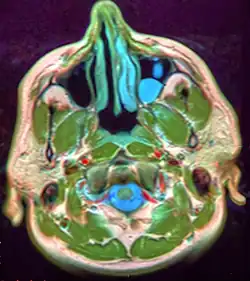

| A mucocele on the lower lip. | |

Mucous extravasation phenomenon is a swelling of connective tissue consisting of a collection of fluid called mucus. This occurs because of a ruptured salivary gland duct usually caused by local trauma (damage) in the case of mucous extravasation phenomenon and an obstructed or ruptured salivary duct in the case of a mucus retention cyst. The mucocele has a bluish, translucent color, and is more commonly found in children and young adults.

The size of oral mucoceles vary from 1 mm to several centimeters and they usually are slightly transparent with a blue tinge. On palpation, mucoceles may appear fluctuant, but can also be firm. Their duration lasts from days to years,[4] and may have recurrent swelling with occasional rupturing of its contents.